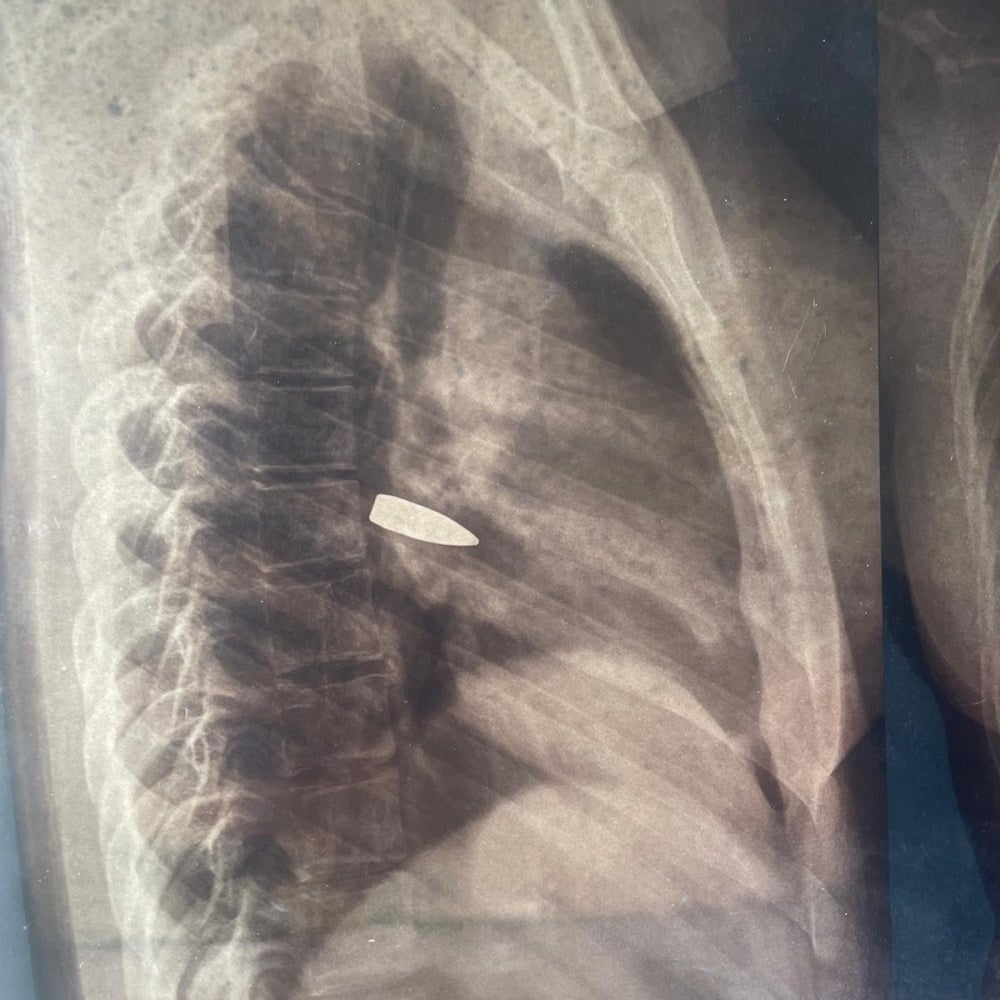

The x-ray image of a 17-year-old girl who was struck in the chest by a stray bullet in the Sénégalais neighborhood, N’Djamena, on May 9, 2024 following the announcement of the provisional results of the Chad presidential elections. © 2024 Private